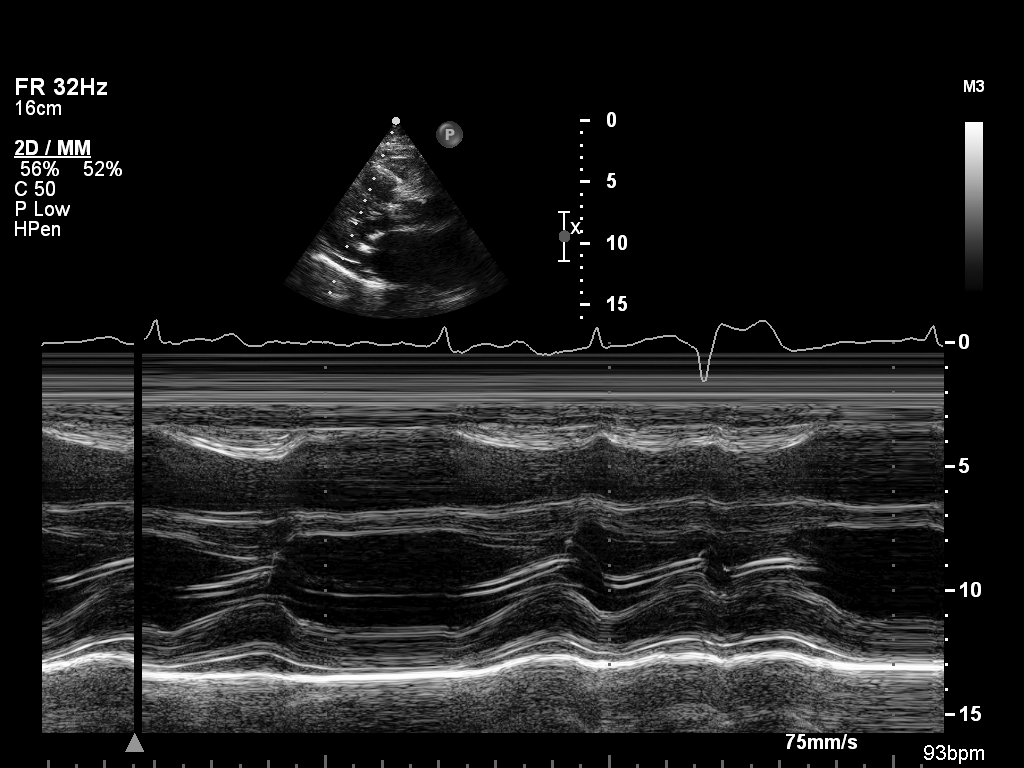

M-mode (5 views)

ImageView NameDescription

mmode-plax-lv mmode-plax-lv M-mode in PLAX focused on LV walls